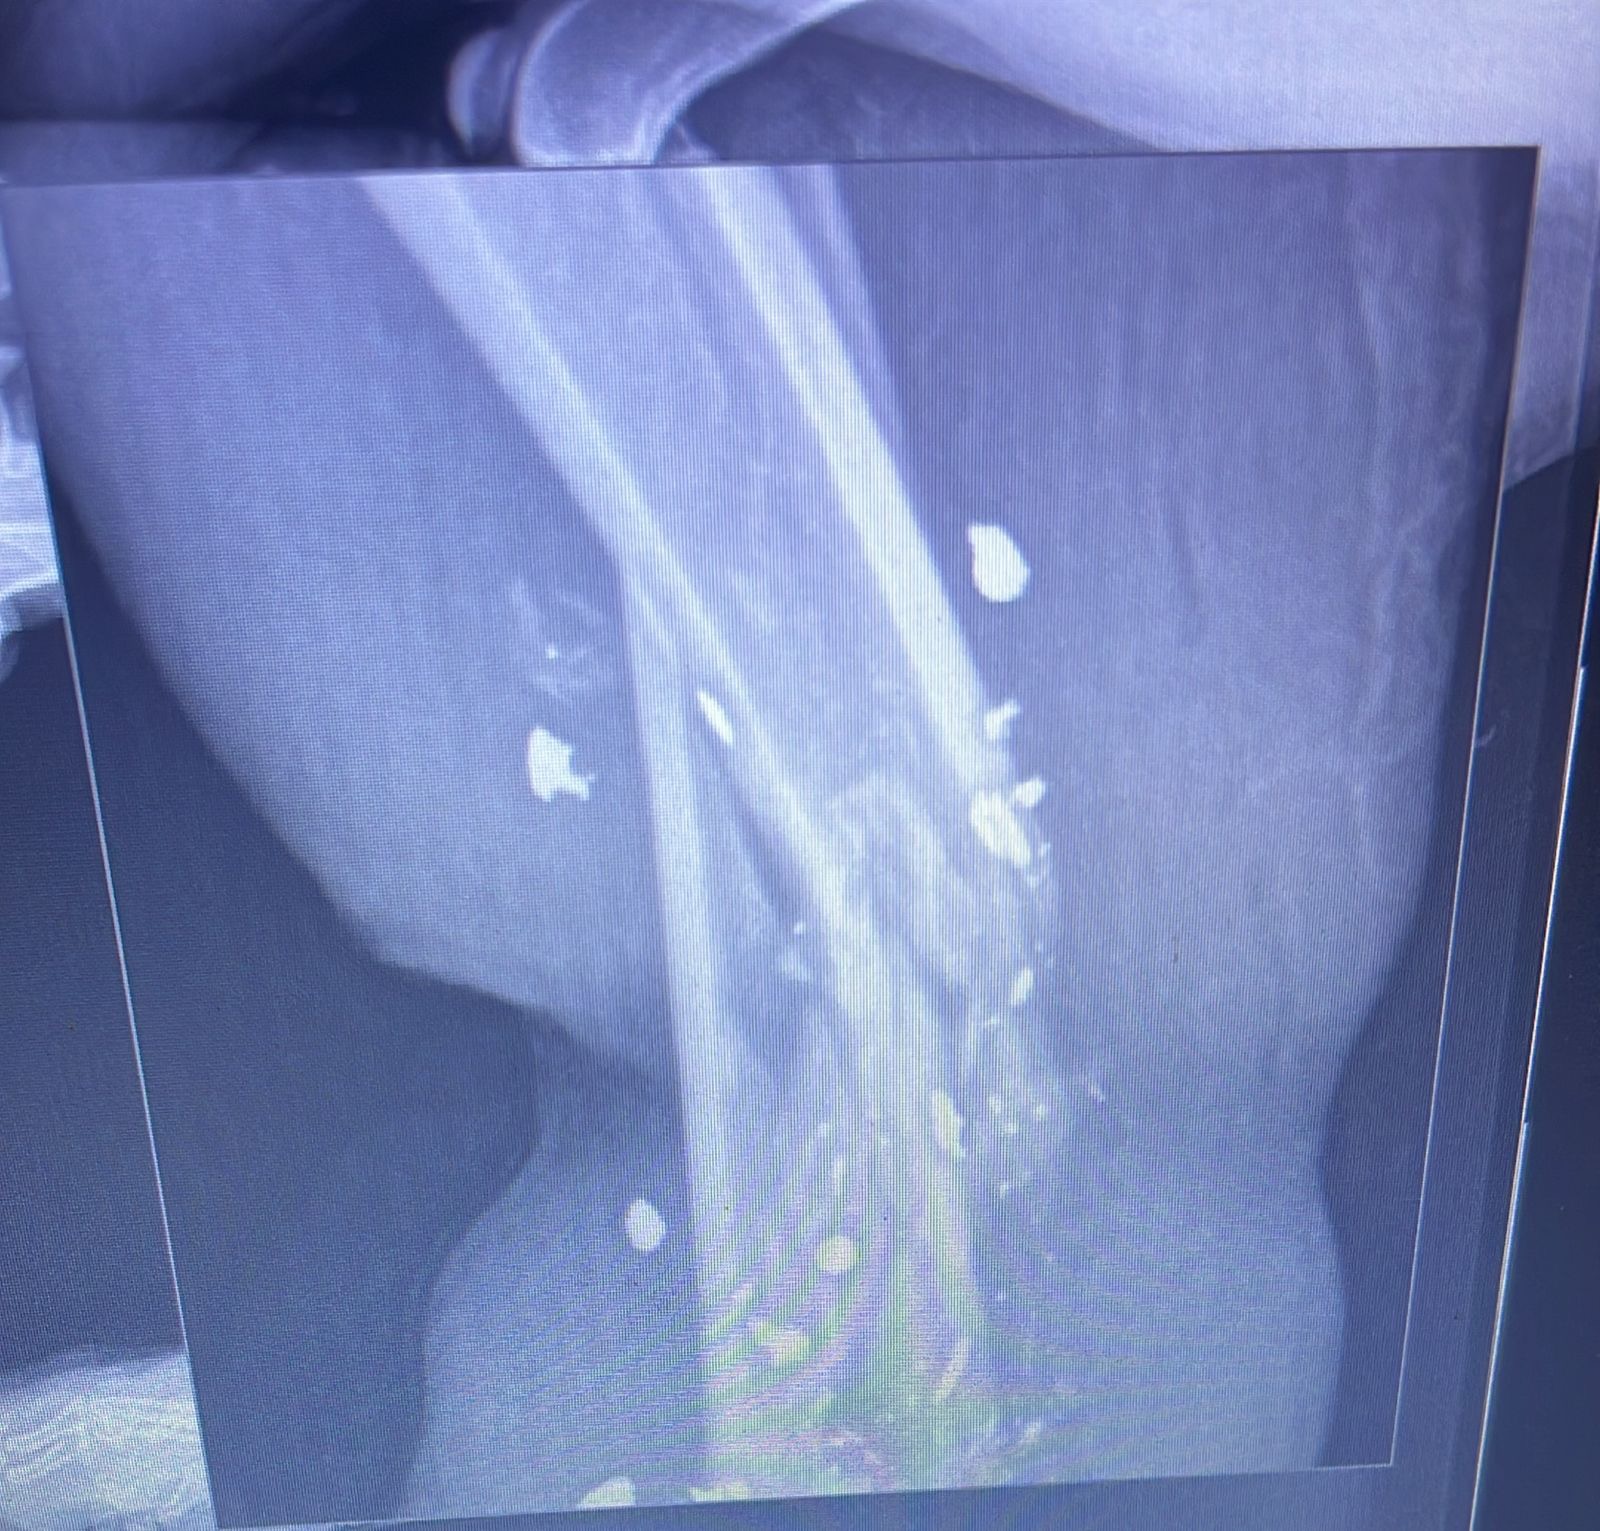

Hello friends and family! This fundraiser is being started for our dog, Pelusa, who was shot in her foot last night. The vet said that the only solution is to amputate her leg since she still has bullet fragments in her leg. Anything is appreciated♥️